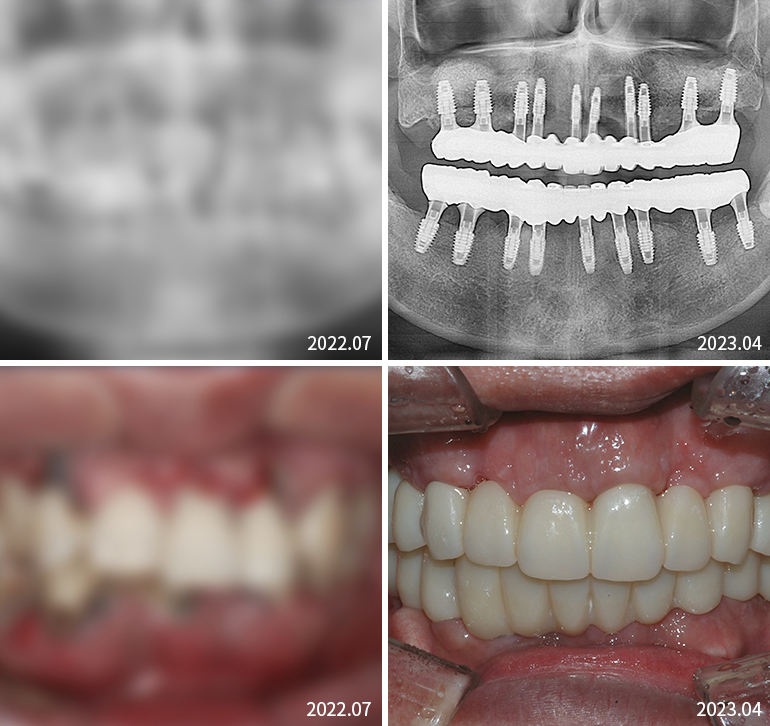

전체임플란트